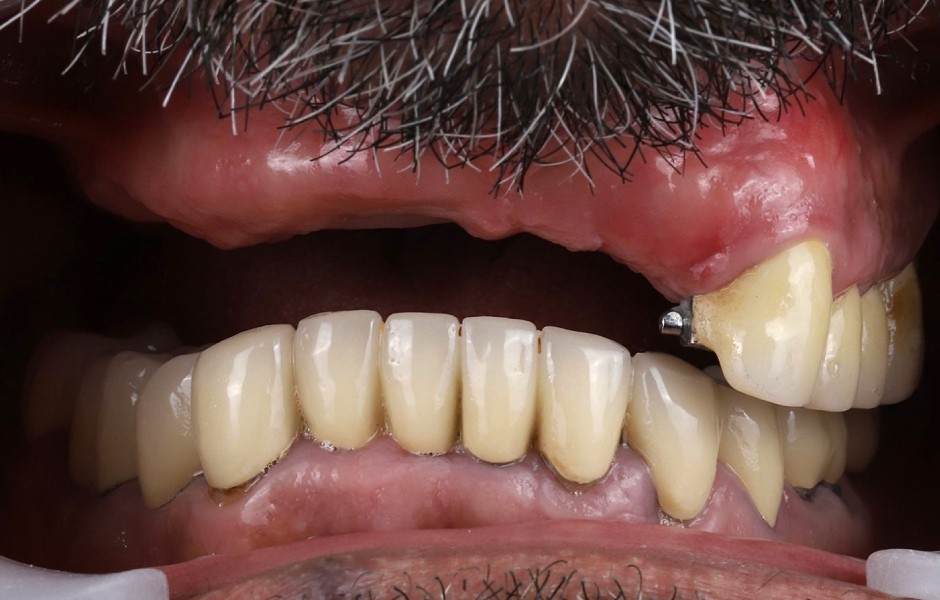

Při extraorální prohlídce nebyly zjištěny žádné významné abnormality. Pacient měl střední úroveň linie úsměvu (obr. 1–3). Po vyjmutí snímatelné náhrady byl odhalen můstek (obr. 4).

Intraorální vyšetření odhalilo starý můstek, který nahrazoval zuby 23 až 26 a zároveň sloužil ke kotvení částečné snímatelné náhrady s kovovou výztuží. Zuby 22 až 17 byly extrahovány již před delší dobou a alveolární hřeben v této oblasti byl zhojen. Nebyl přítomen plak ani zánět. Zuby vykazovaly mírnou až střední ztrátu attachmentu, ale nebyly pozorovány žádné parodontální léze nebo fraktury kořenů (obr. 5–8).

Obr. 1, 2

Obr. 3, 4

Obr. 5

Obr. 6

Obr. 7

Obr. 8